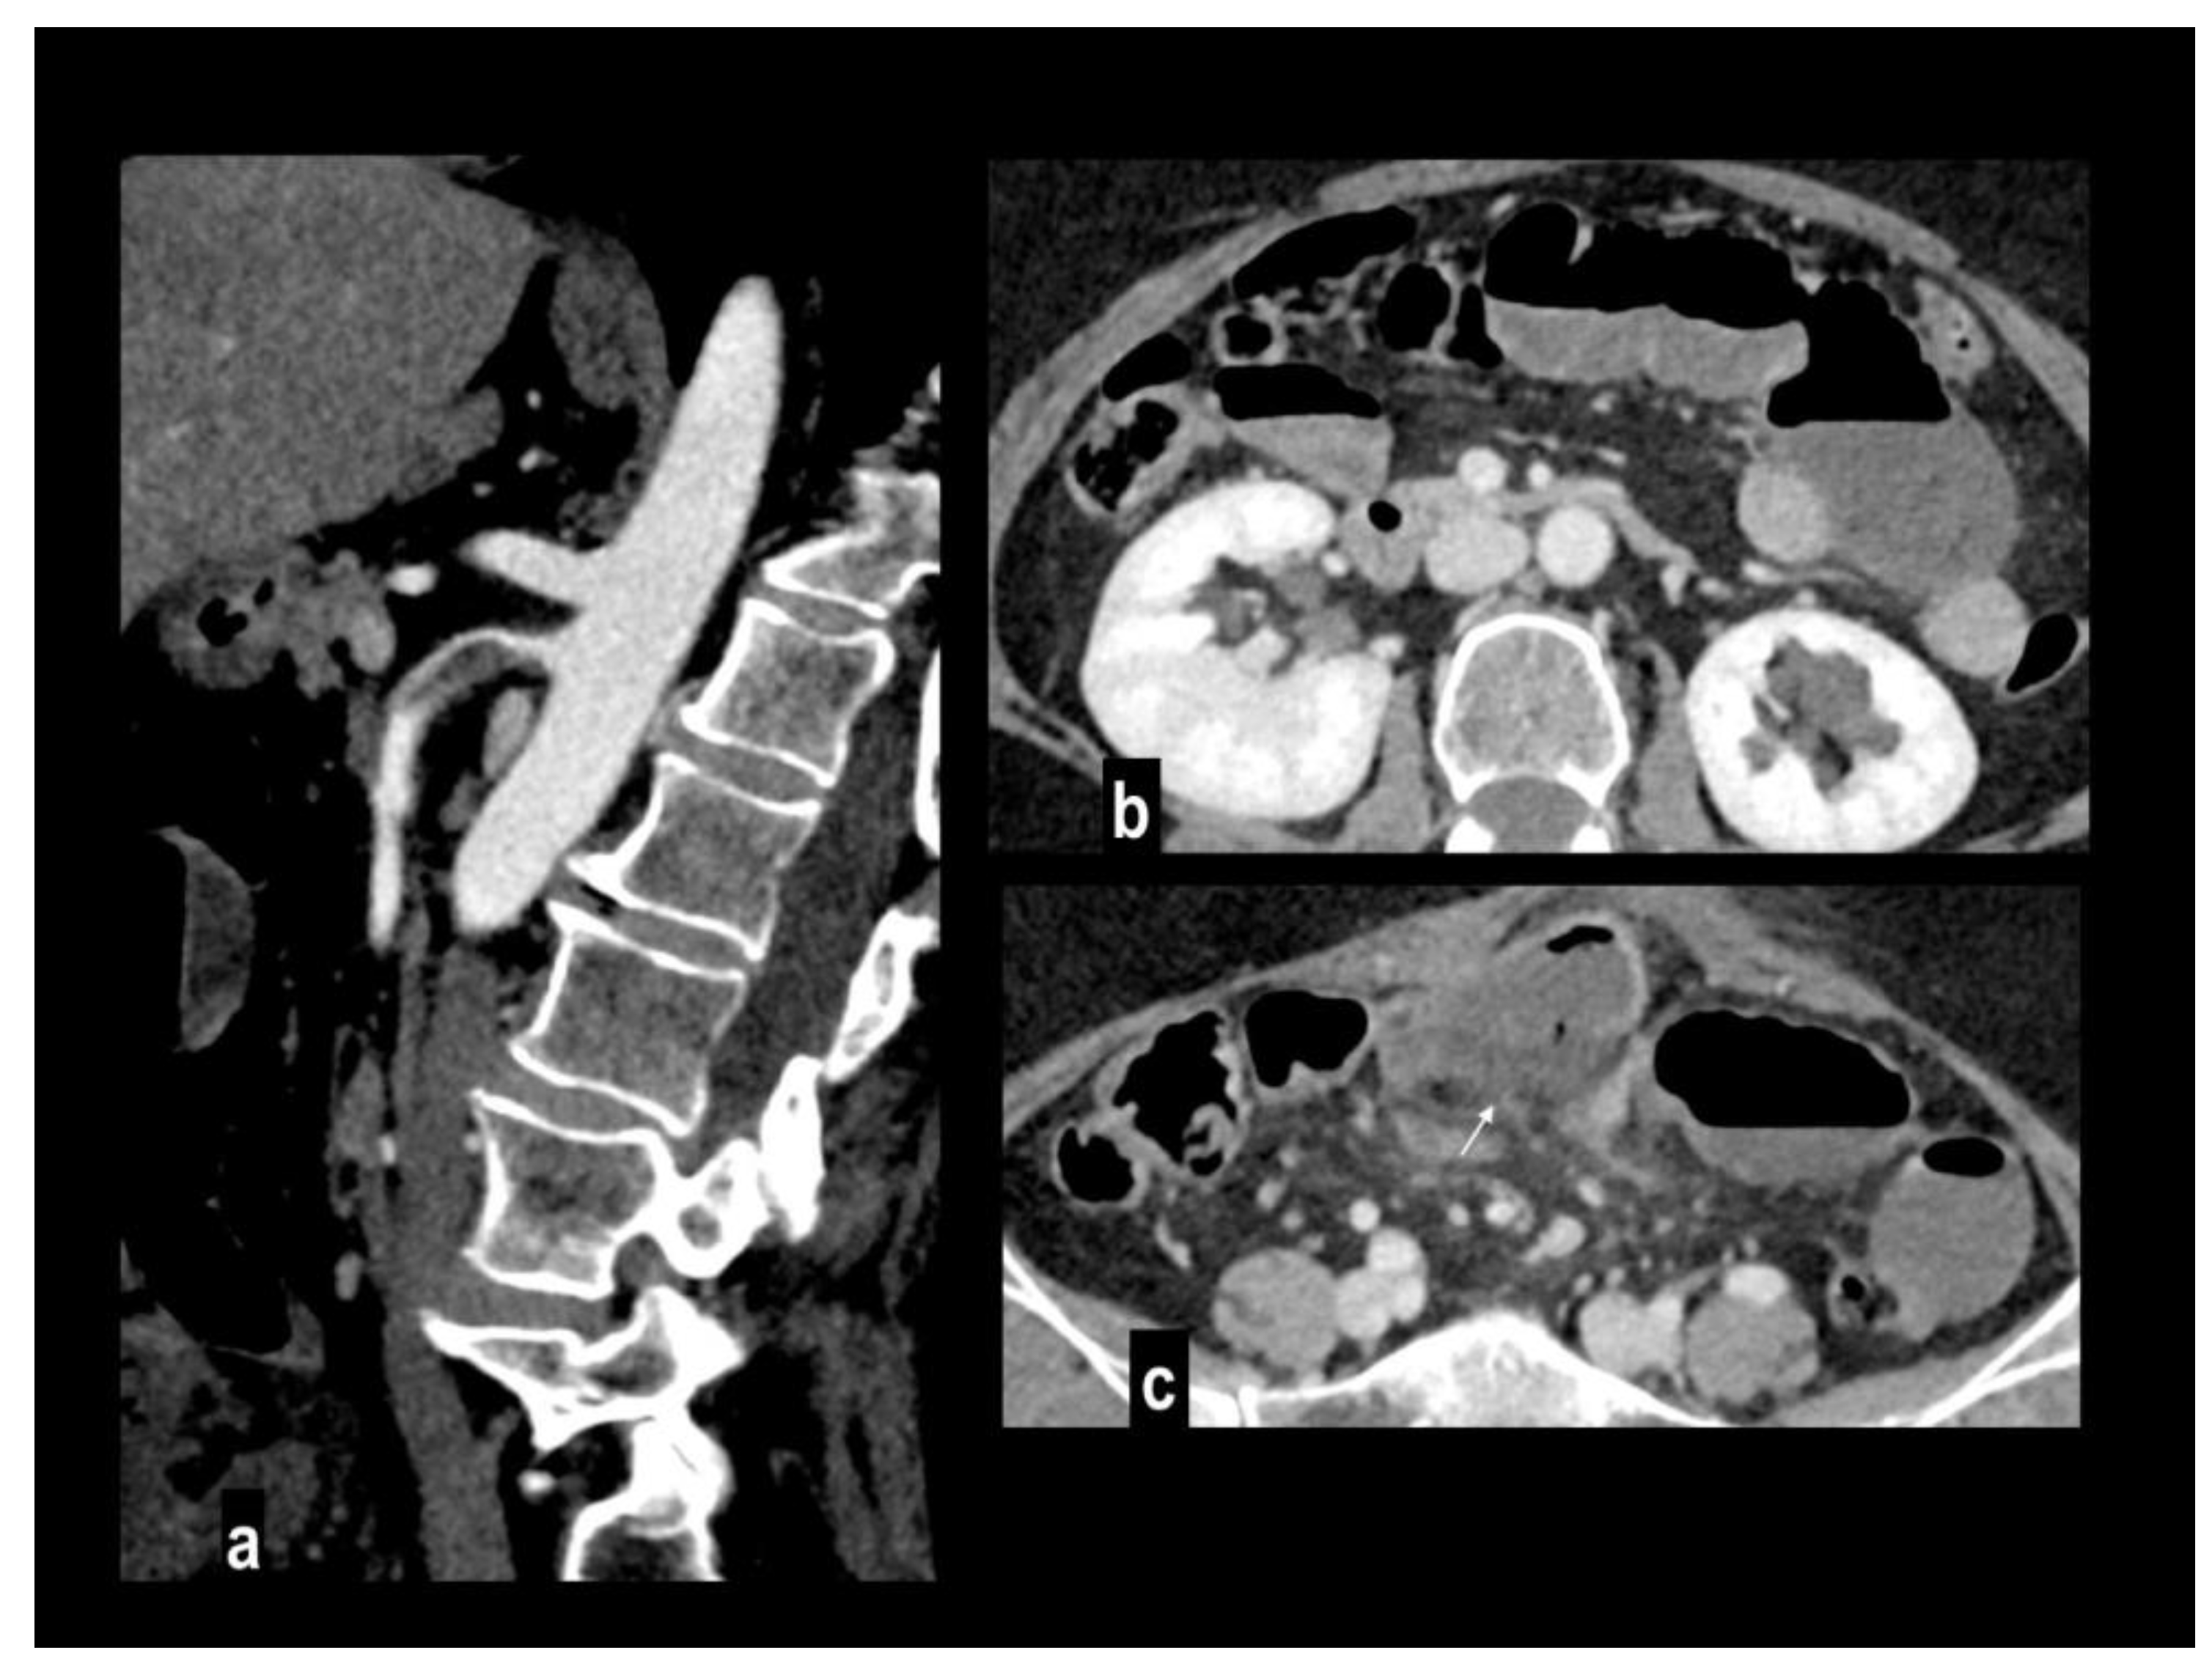

Figure 3. Acute abdominal pain in a 52-year-old with atrial fibrillation. Oblique sagittal and coronal MIP arterial images showed embolic occlusion of the middle SMA, with subtle peripheral segmentary enhancement of distal lumen by a collateral vessel (figure 3a-b). Hypoenhancing ileal and right colon walls were well appreciated in comparison to jejunal loops on left abdominal side (figure 3c). A left renal infarct is also present (figure 3d). Patient underwent a right colectomy.

Preprints 106216 g003aPreprints 106216 g003b